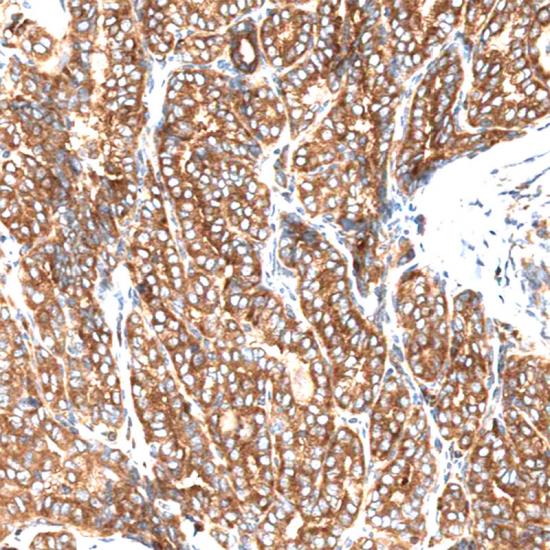

BRAF(V600E)

BRAF抗體試劑(免疫組織化學(xué)) 閩廈械備20180154號(hào)

• 陽性部位:

細(xì)胞漿

• 陽性對(duì)照:

甲狀腺癌

BRAF是人類最重要的原癌基因之一,大約8%的人類腫瘤發(fā)生BRAF突變。BRAF絕大部分突變形式為BRAF(V600E)突變,主要發(fā)生于黑色素瘤、結(jié)腸癌和甲狀腺癌中。該突變導(dǎo)致下游MEK-ERK 信號(hào)通路持續(xù)激活,對(duì)腫瘤的生長(zhǎng)增殖和侵襲轉(zhuǎn)移至關(guān)重要,是抗黑色素瘤等BRAF(V600E)突變腫瘤特效新藥Vemurafenib和Dabrafenib的有效作用靶標(biāo)之一。